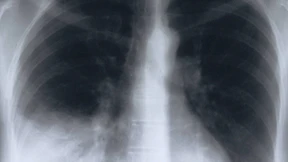

Der Medizin-Nobelpreis geht im diesem Jahr an die Krebsforscher James Allison und Tasuku Honjo. Sie haben entdeckt, wie sich das Immunsystem so stimulieren lässt, dass es Tumorzellen angreift. Eine Sensation.